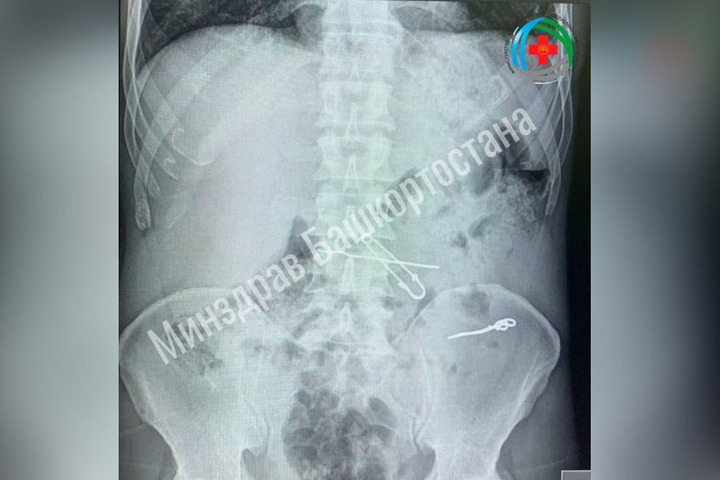

В Уфе врачи больницы скорой медицинской помощи спасли жизнь мужчине, который проглотил проволоку и скрепки. Об этом сообщил в соцсетях министр здравоохранения Айрат Рахматуллин.

Пациент поступил в медучреждение с болями в животе. Исследования показали наличие в его организме инородных предметов длиной 47,62 и 90 мм. Хирурги провели операцию, удалив из кишечника проволоку и скрепку, а из желудка – булавку и проволоку. Пациент пошел на поправку и вскоре отправился для восстановления домой.